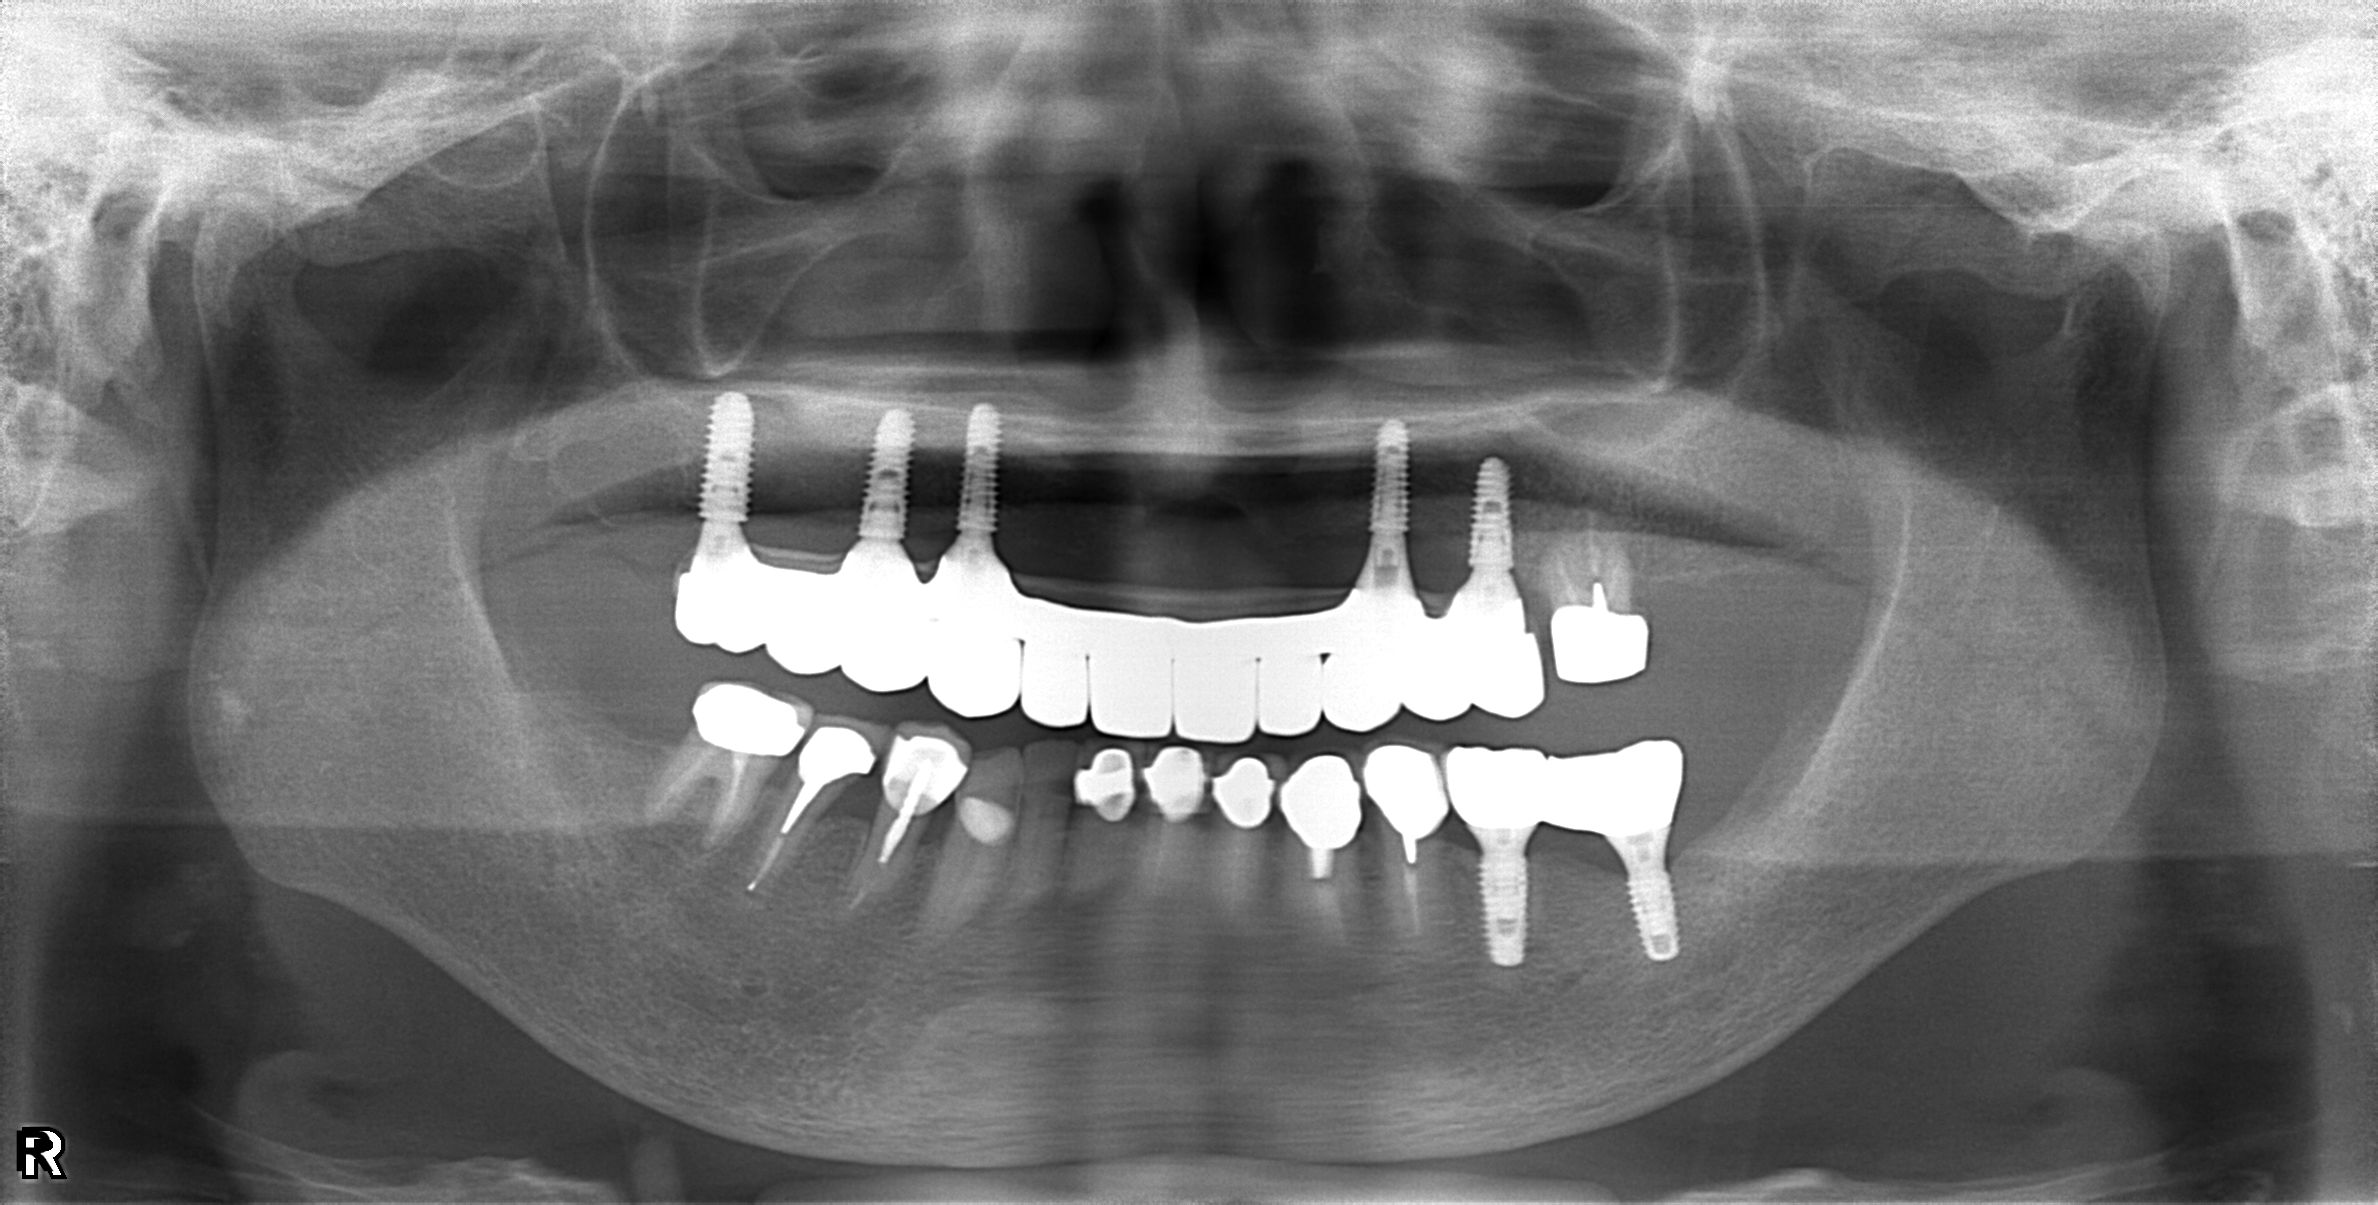

案例-上顎

醫生透過電腦斷層及全口X光照片評估骨頭狀況決定植入的植體數量、寬度以及深度

當天有臨時假,鎖上並封填

大約3-4的癒合時間,把臨時假牙取下

鎖上正式假牙

完成!